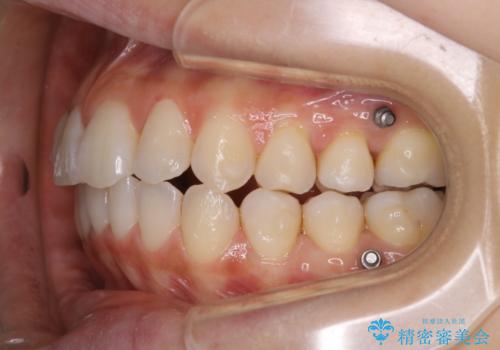

インビザラインの矯正中の方でアタッチメントが歯に付いているため、2ヶ月で着色やプラークが付いてきてしまいました。ホームケアや飲食の仕方により個人差はありますが、基本的には汚れが普段よりもつきやすいです。